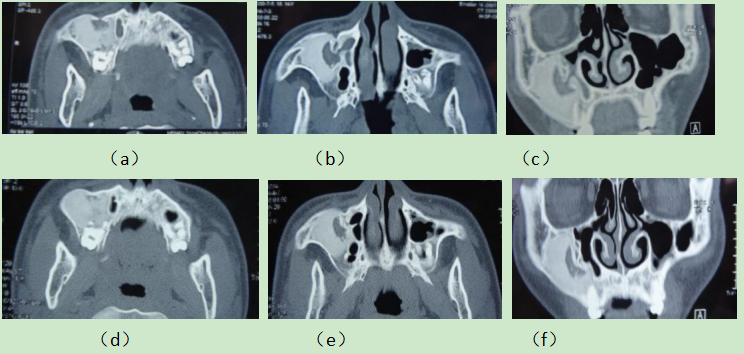

病例2,男,23岁,右侧上颌骨纤维异样增殖症。右面部明显肿大,疼痛5年。 CT显示右上颌骨和上颌窦区域骨纤维异样增殖症,治疗9个月恢复正常。

治疗前(a--c),右上颌和上颌窦区域存在多个斑块状的毛玻璃密度混合阴影,颌窦区域腔隙变小。

治疗后(d--f),右上颌骨和右上颌窦区域的骨纹理清晰,密度均匀,颌窦区域空腔增大。

Case 2, male, 23 years old, right face significantly enlarged, pain for 5 years. CT showed dysplasia of bone fibers in the right maxilla and maxillary sinus area, which recovered after 9 months.

Before eating (a) - (c), there were multiple patchy ground glass density mixed shadows in the right maxilla and the maxillary sinus area, which grew expansively and the cavity became smaller. After eating (d) - (f), the bone texture of the right maxillary and the right maxillary sinus area was clear, and the cavity increased.